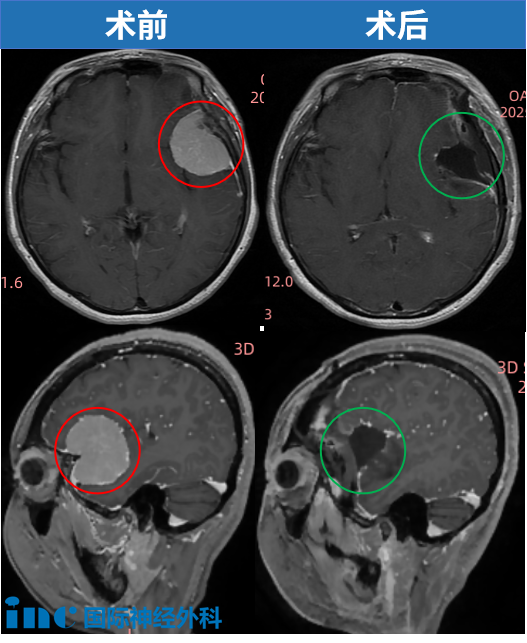

"开颅手术后,我竟然这么快就清醒了!"在苏州大学附属第四医院ICU,刚刚经历开颅手术仅数小时的安女士,用清晰的语言和灵活的手脚动作,让所有人惊喜不已。“说话完全没问题,手脚活动也正常,精神状态比想象中好太多了,非常非常感谢巴教授!”当巴特朗菲教授亲自查房,确认肿瘤已完全切除时,这位38岁的脑膜瘤患者激动不已——她知道,自己做出了人生中正确的选择。就在安女士术后第7天,她顺利出院!

深入咨询INC后,巴教授过往成功案例让她坚定选择。全切肿瘤、无神经损伤——尤其得到巴教授关于这两个关键指标的评估,完全符合她的治疗诉求。更幸运的是,恰逢巴教授在国内进行示范手术。

术中,为了降低复发率,巴教授切掉了肿瘤起源的硬脑膜。教授用她大腿上的筋膜代替脑膜,把洞补齐。

手术精准高效:只剃切口范围内1cm处头发、不影响美观,全切肿瘤,恢复迅速——术后7天出院。